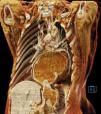

Una mujer de 70 años con antecedente de carcinoma neuroendocrino de células grandes y pequeñas con componente focal de adenocarcinoma de endometrio metastásico a pulmón y antecedente de hernia hiatal grande (>5cm) (fig. 1), ingresó a urgencias por un dolor torácico opresivo, irradiado a cuello y exacerbo con la ingesta de alimentos. Los laboratorios a su ingreso reportaron leucocitos 21.3 ×109/L, neutrófilos 18.3 ×109/L, proteína C reactiva 37.8mg/dL, deshidrogenasa láctica (DHL) 241 UI/L y lactato 2.7 mmol/L; la evaluación de cardiaca sin alteraciones y angiotomografía negativa para tromboembolia pulmonar, sin embargo, se evidenció una hernia hiatal en posición de espejo (fig. 2). Se descomprimió con sonda nasogástrica y ante la sospecha de estrangulación gástrica fue sometida a reducción de hernia hiatal y gastropexia laparoscópica, con mejoría sintomática del dolor. Las hernias del hiato se dividen en cuatro tipos, siendo las más complejas las paraesofágicas (tipo III y IV) que representan el 5-10% (fig. 3). Este tipo de hernias pueden llegar a contener además del estómago, otras vísceras abdominales como el colon, el intestino delgado, el páncreas o el bazo. Las complicaciones agudas como estrangulación o isquemia ameritan descompresión inmediata.